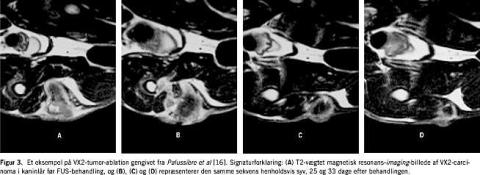

Palussière et al har påvist effektiviteten af MRI-kontrolleret FUS-hypertermi med kontinuerlig sonikering til behandling af VX2-karcinomtumorer implanteret i lårbensmuskler [16]. Små fragmenter af VX2-tumorer blev dyrket i nøgne mus og implanteret i et lår på new zealandske kaniner. 60% af kaninerne gennemgik FUS-behandling, efter at de respektive tumorer var større end 2 cm (10-21 dage efter implantationen). FUS-metoden var baseret på bevægelse af fokuspunktet langs en spiralbane med konstant FUS-effekt og automatisk realtids-MRI-kontrol. Den totale varmeperiode var ca. 16 minutter, og effektiviteten af behandlingen blev efterfølgende evalueret to gange om ugen baseret på kliniske data og MRI-data. De behandlede kaniner blev aflivet fem uger efter proceduren, hvorefter histologiske undersøgelser blev udført. Tumorregression blev observeret hos alle de behandlede dyr. Total ablation, underbygget med histologi, blev registreret i 85% af tilfældene (Figur 3 ). I et tilfælde blev der registreret tumorrevitalisering. Hos 50% af dyrene var den varmeinducerede skade fuldstændig begrænset til tumoren, mens der hos de resterende 50% også blev observeret skader på dele af det omkringliggende væv. Der blev generelt fundet god korrelation mellem in vivo-MRI og histologisk identifikation af beskadiget tumorvæv.